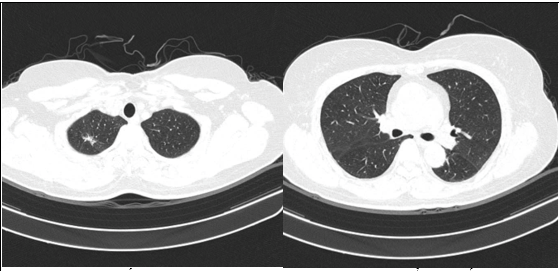

- Chụp cắt lớp vi tính lồng ngực: Nhu mô thùy trên phổi (Phải) có nốt tổn thương kích thước 13x14mm,bờ không đều, ngấm thuốc, sau tiêm. Rải rác nốt đặc 2 bên thùy phổi kích thước 3-10mm. Trung thất các nhóm 1R; 2R; 4R; 5; 8; 10RL có vài hạch lớn nhất kích thước 26x15mm; bờ không đều; ngấm thuốc không đồng nhất sau tiêm. Thượng đòn 2 bên có vài hạch tính chất tương tự; hạch bên phải kích thước 11x14mm

Hình 1.

Hình ảnh cắt lớp vi tính ngực có tiêm: thùy trên phổi (P) có nốt tổn thương kích thước 13x14mm, bờ không đều, ngấm thuốc, sau tiêm. Nghi ngờ tổn thương nguyên phát (mũi tên đỏ)

Hình 2: Hình ảnh cắt lớp vi tính ngực có tiêm: Rải rác nốt đặc 2 bên thùy phổi kích thước 3-10mm (các mũi tên màu xanh lá)

Hình 3: Hình ảnh cắt lớp vi tính ngực có tiêm: Trung thất các nhóm 1R; 2R; 4R; 5; 8; 10RL có vài hạch lớn nhất kích thước 26x15mm; bờ không đều; ngấm thuốc không đồng nhất sau tiêm (mũi tên màu cam)

- Cắt lớp vi tính lồng ngực: đám xẹp đông đặc đỉnh phổi phải kích thước 11mm; nhu mô phổi rải rác nốt đặc 5-10mm. Trung thất cân đối có vài hạch 10mm

Hình 6: Hình ảnh cắt lớp vi tính ngực có tiêm: đám xẹp đông đặc đỉnh phổi phải kích thước 11mm (mũi tên xanh nước biển)

Hình 7: Hình ảnh cắt lớp vi tính ngực có tiêm: Trung thất cân đối có vài hạch 10mm (mũi tên vàng). Hạch trung thất giảm kích thước rất nhiều chỉ sau 03 chu kỳ.

- Cắt lớp vi tính lồng ngực: Đám xẹp vùng đỉnh phổi phải, nốt đặc nhỏ kích thước 2-3mm. Không thấy hạch to hay khối trong trung thất

Hình 10: Hình ảnh cắt lớp vi tính ngực có tiêm: Đám xẹp vùng đỉnh phổi phải, nốt đặc nhỏ kích thước 2-3mm

Hình 11: Hình ảnh cắt lớp vi tính ngực có tiêm: Không thấy hạch to hay khối trong trung thất

Nhận xét: Chỉ sau 03 chu kỳ Pemetrexed – Carboplatin – Pembrolizumab, hình ảnh chụp cắt lớp vi tính cho thấy tổn thương phổi nguyên phát và các hạch giảm kích thước đáng kể. Đáp ứng điều trị được đánh giá là đáp ứng một phần theo tiêu chuẩn RECIST 1.1. Sau 9 chu Pemetrexed – Pembrolizumab, bệnh nhân tiếp tục ghi nhận cải thiện rõ rệt các triệu chứng lâm sàng, thể trạng ổn định, không xuất hiện tác dụng không mong muốn nghiêm trọng.Đánh giá trên hình ảnh chụp cắt lớp vi tính cho thấy tổn thương phổi nguyên phát tiếp tục giảm kích thước không ngấm thuốc chỉ còn là đám xơ xẹp vùng đỉnh phổi phải, các hạch trung thất và ngoại vi thu nhỏ rõ rệt, không phát hiện được trên phim chụp và không ghi nhận tổn thương di căn mới.